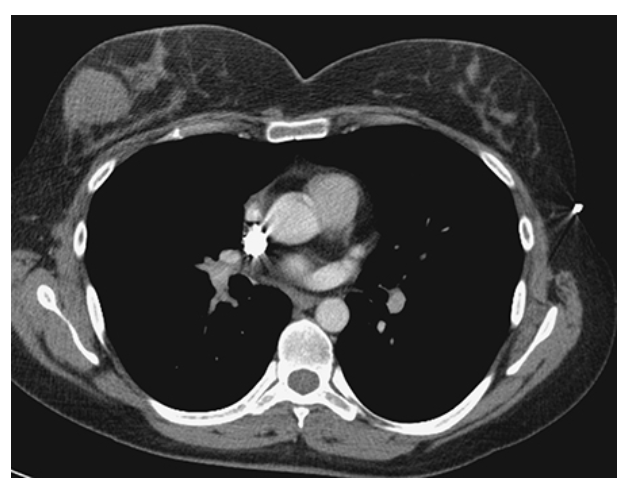

Pericardial Effusion. Contrast-enhanced CT (CECT) shows increased fluid density around the heart consistent with a pericardial effusion.